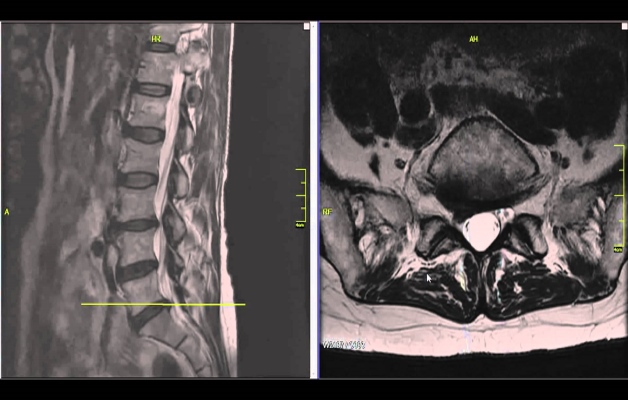

Чтобы уточнить диагноз, после беседы, визуального и пальпаторного обследования больного отправляют на аппаратную диагностику:

- Компьютерную томографию – показывает просвет спинномозгового канала, грыжи, врожденные аномалии, состояние сосудов и мягких тканей.

- Магнитно-резонансную томографию – назначается в случаях, когда другие методы дали спорный результат или вообще мало что показали. МР-картина патологии самая точная, однако этот вид диагностики и самый дорогостоящий.